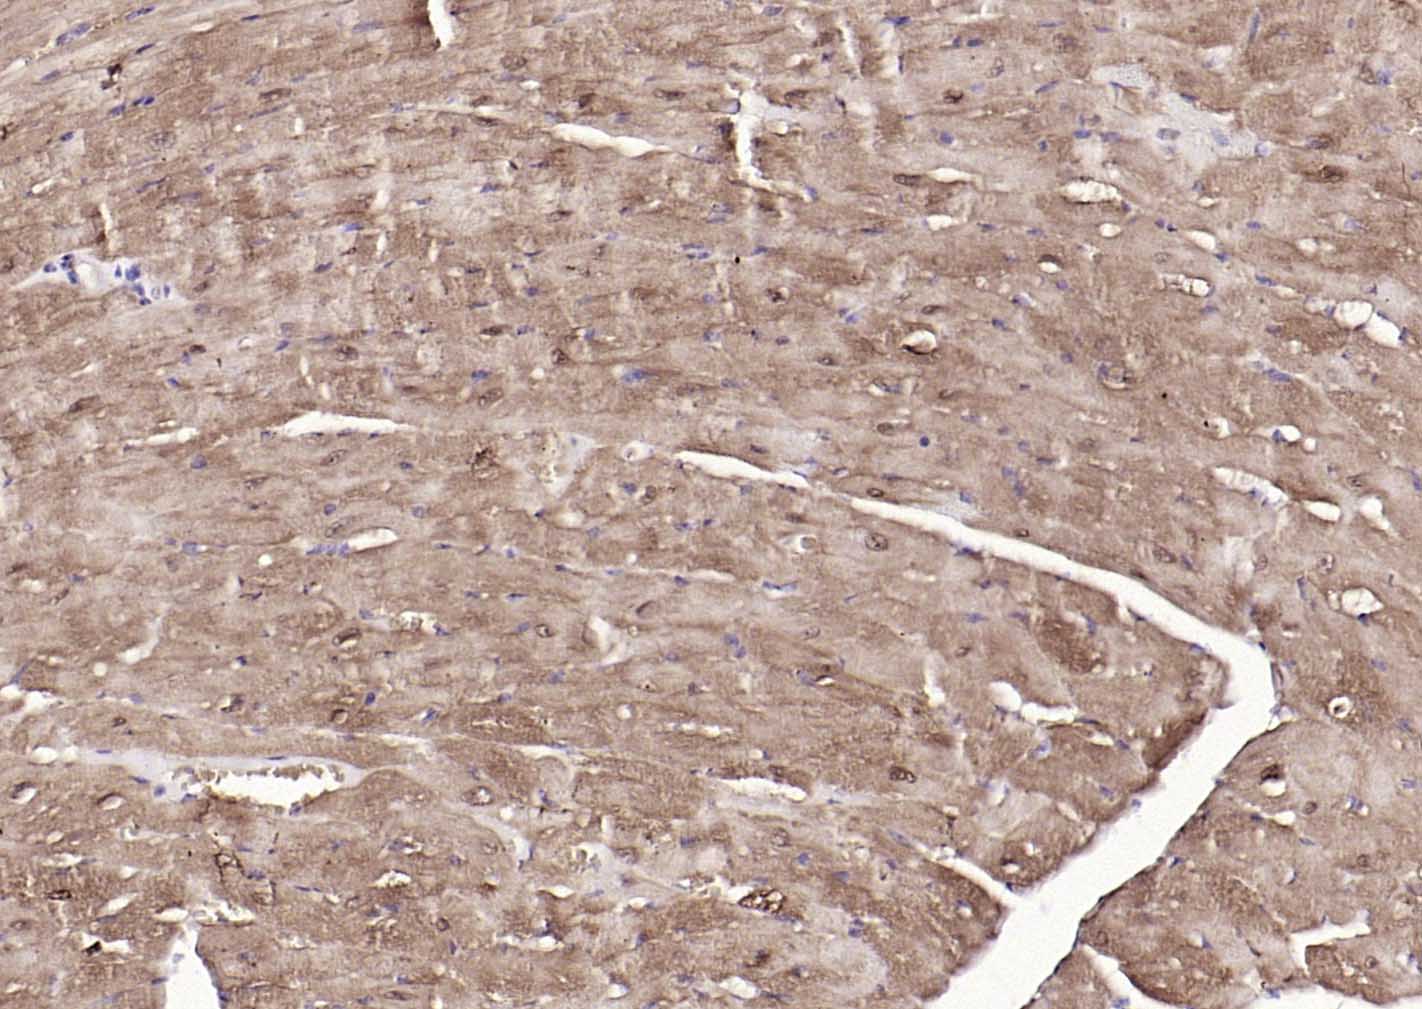

Paraformaldehyde-fixed, paraffin embedded (rat heart); Antigen retrieval by boiling in sodium citrate buffer (pH6.0) for 15min; Block endogenous peroxidase by 3% hydrogen peroxide for 20 minutes; Blocking buffer (normal goat serum) at 37°C for 30min; Incubation with (S100A1 ) Polyclonal Antibody, Unconjugated (bs-41209R) at 1:200 overnight at 4°C, followed by operating according to SP Kit(Rabbit) (sp-0023) instructionsand DAB staining.

Paraformaldehyde-fixed, paraffin embedded (mouse heart); Antigen retrieval by boiling in sodium citrate buffer (pH6.0) for 15min; Block endogenous peroxidase by 3% hydrogen peroxide for 20 minutes; Blocking buffer (normal goat serum) at 37°C for 30min; Incubation with (S100A1 ) Polyclonal Antibody, Unconjugated (bs-41209R) at 1:200 overnight at 4°C, followed by operating according to SP Kit(Rabbit) (sp-0023) instructionsand DAB staining.